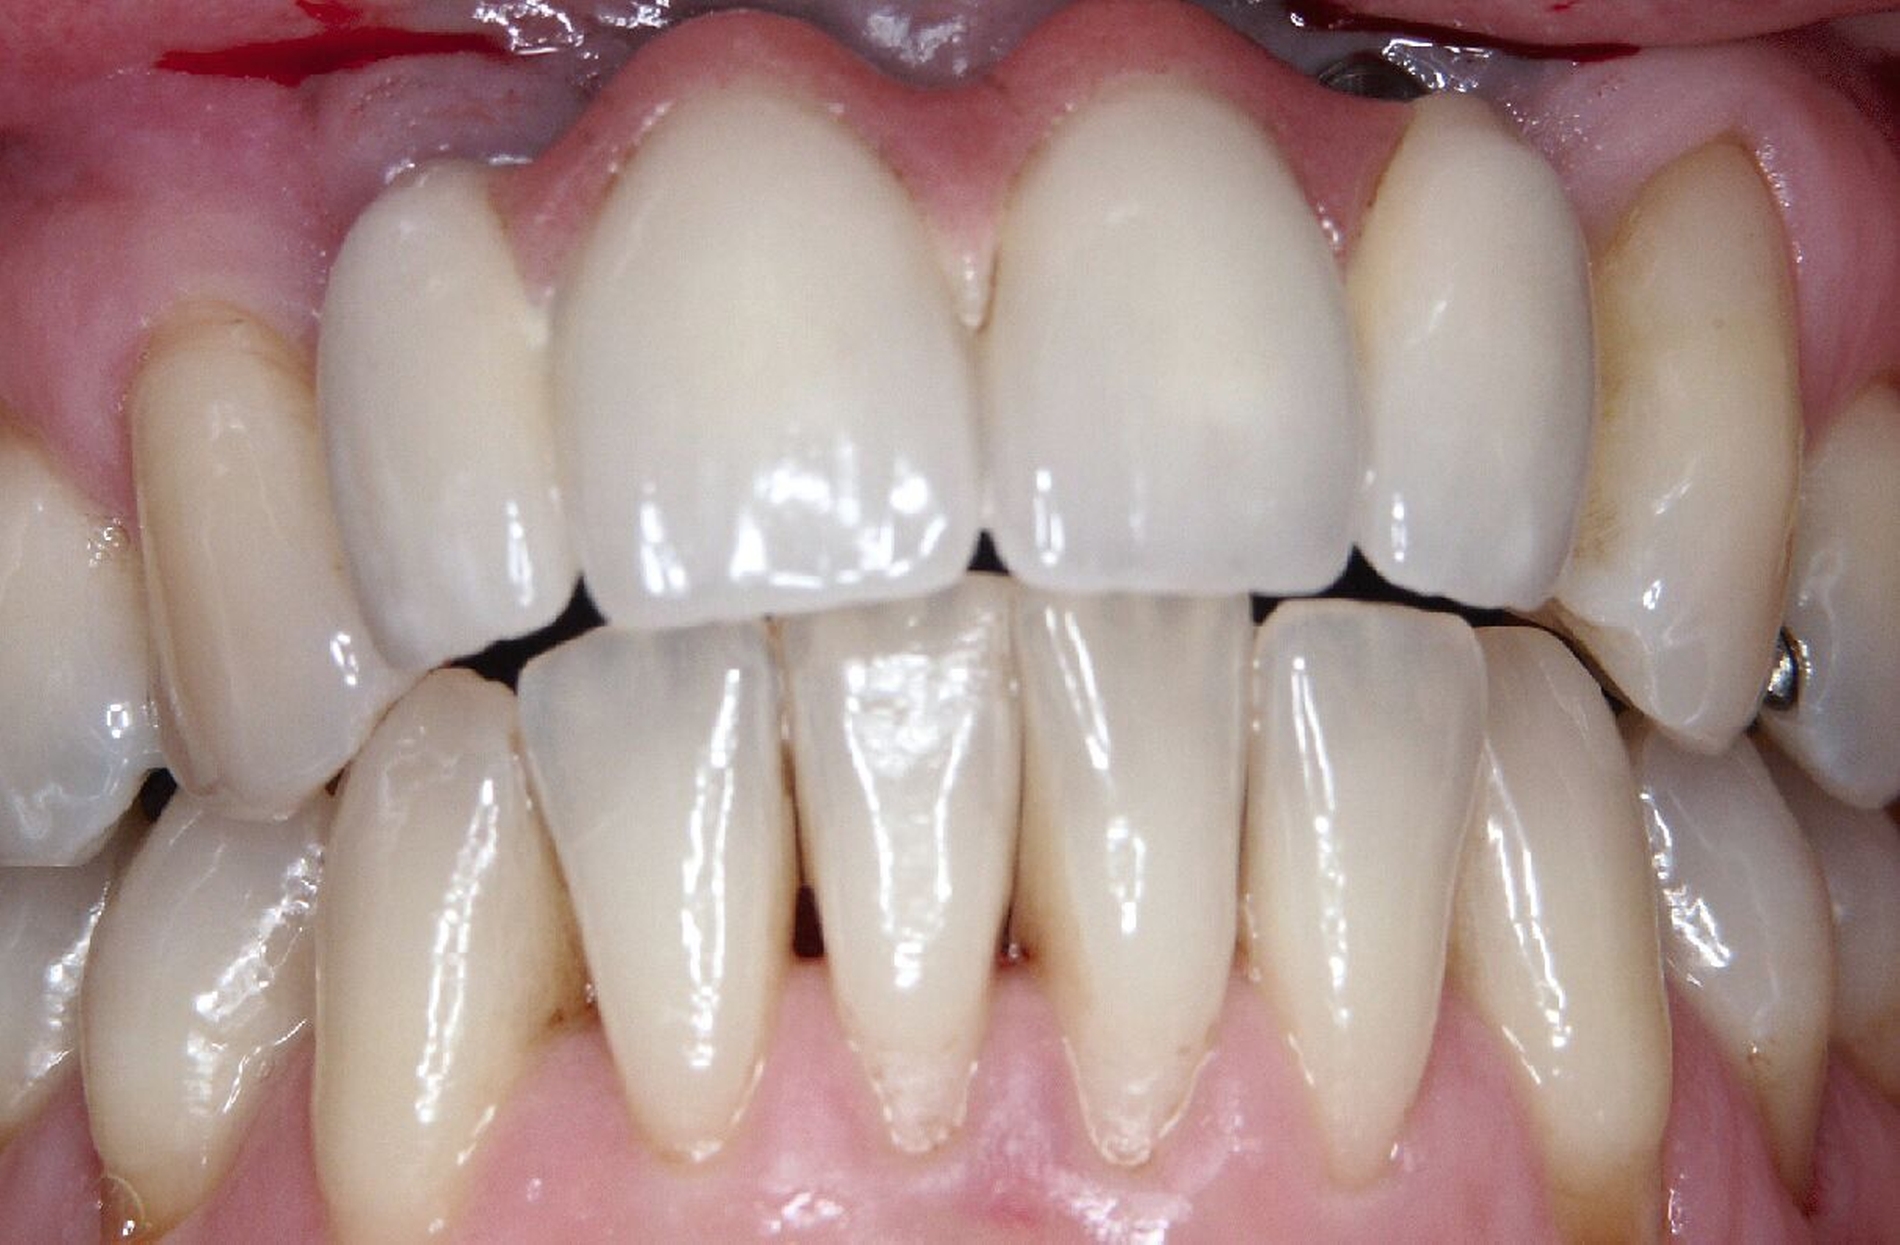

Ursprünglich waren bei dieser Patientin nach einem Frontzahntrauma vier Implantat-gestützte Kronen geplant. Nach dem frühen Verlust des Implantats in regio 21 während der Einheilzeit wurde dann eine auf drei Implantaten abgestützte Brücke eingegliedert. Das bestehende vertikale und horizontale Weichgewebsdefizit wurde bei der verschraubten Implantatbrücke durch aufgebrannte rosafarbene Keramik kaschiert (Abb. 3a). Funktionell war die Brückenversorgung über viele Jahre erfolgreich und zeigte keinerlei Lockerungsgrad. Trotz guter Mundhygiene war in Kontrollsitzungen ein kontinuierlicher Knochenabbau an allen Implantaten festzustellen (Abb. 3b). Zur Vermeidung eines weiteren Knochenverlusts fiel circa 15 Jahre nach der Erstversorgung die Entscheidung zur Explantation. Zu diesem Zeitpunkt war die Patientin 55 Jahre alt.

Nach dem Abschrauben der Suprastruktur (Abb. 3c und 3d) wurden alle Implantate unter Lokalanästhesie mit einem passenden Trepanbohrer umbohrt und ohne Lappenbildung entfernt. Die temporäre Lückenversorgung erfolgte mit einer herausnehmbaren Prothese, die über Gussklammern am Restgebiss abgestützt war.

Da sechs Monate nach der Explantation keine nennenswerte knöcherne Regeneration festzustellen war, wurde eine zweizeitige Implantation nach Knochenaugmentation mithilfe dünner Knochenscheiben aus dem Kieferwinkel geplant. Die Entnahme erfolgte mit oszillierenden Instrumenten (Piezosurgery). Der Knochenblock wurde in dünne Scheiben geschnitten und mit Osteosyntheseschrauben am Alveolarfortsatz fixiert (Abb. 3e). Darüber wurden die Weichgewebe dicht vernäht. Weitere fünf Monate später erfolgte die Schraubenentfernung und die Implantation von zwei Bone-Level-Implantaten in regio 12 und 22 mit geschlossener Einheilung (Abb. 3f und 3g). Bei der Implantatfreilegung weitere sechs Monate später wurden die Weichgewebsdefizite im Brückengliedbereich durch ein kombiniertes Bindegewebs-/Schleimhauttransplantat aufgefüllt und gleichzeitig die keratinisierte periimplantäre Gingiva und Alveloarmukosa verbreitert (Abb. 3h und 3i). Die prothetische Versorgung erfolgte erst weitere drei Monate später, nach dem Konsolidieren der Weichgewebe. Die umfangreichen Augmentationsmaßnahmen konnten das transversale Weichgewebsdefizit vollständig kompensieren, während das verbleibende vertikale Defizit zu zervikal etwas längeren Kronen und Brückengliedern führte. Aufgrund der guten Abdeckung durch die Oberlippe kann das ästhetische Ergebnis als zufriedenstellend bewertet werden (Abb. 3j bis 3l).